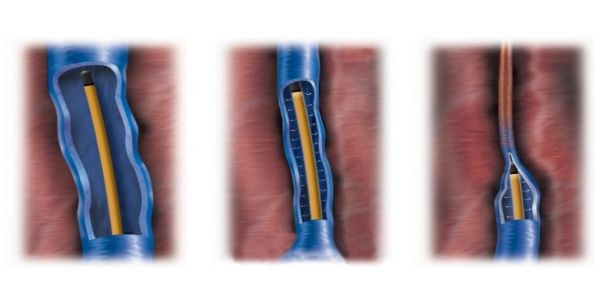

基本的には皮膚に注射をして行うため、皮膚を切る必要がありません。カテーテルから高周波で熱を発生させ行います。

- ※画像の無断転用は禁止です

血管内焼灼術と同様、皮膚を切る必要がありません。

カテーテルから瞬間接着材(シアノアクリレート)を血管内に注入します。